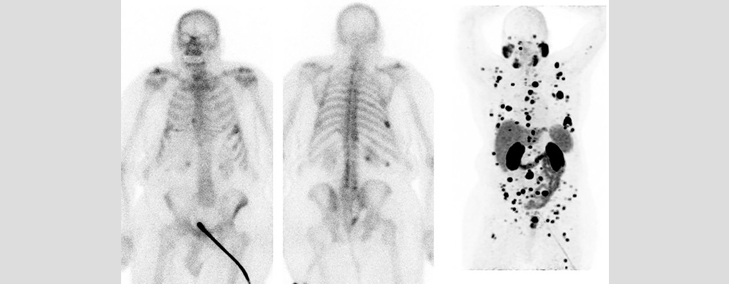

PSMA PET

An PSMA PET-CT SCAN uses a radiotracer which targets and attaches to the molecule PSMA (prostate specific membrane antigen) in the body. In this scan, a small amount of radiotracer is injected in the body and its distribution is seen in the body using the PET-CT scanner.

A PSMA PET-CT SACN is commonly used for evaluation of patients with prostate cancer. However, PSMA PET-CT SCANNING is a new technology and further new uses are being evaluated.